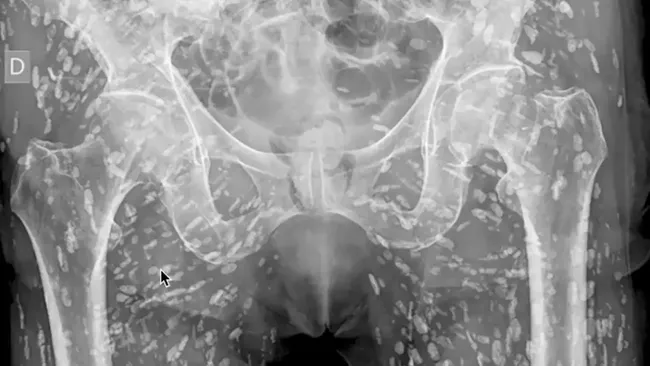

Pasien yang dipenuhi cacing pita (Foto: Tangkapan Layar X)

Dr Sam Ghali seorang dokter dari University of Florida College of Medicine di Jacksonville membagikan hasil foto rontgen pasien, yang jaringan lunak tubuhnya dipenuhi parasit.

Diunggah di media sosial X, Sam menunjukkan foto tubuh pasien yang dipenuhi bintik-bintik lonjong, yang tak terhitung jumlahnya. Ia menyebut hasil X-ray itu yang paling 'gila' yang pernah ia lihat.

Dikutip dari detikHealth, kondisi ini dikenal sebagai cysticercosis. Ini adalah infeksi parasit yang disebabkan oleh kista larva dari cacing pita, atau Taenia solium. Pasien yang tidak disebutkan namanya ini terinfeksi setelah mengonsumsi daging babi yang mentah atau kurang matang.

Dalam kasus pasien ini, kista parasit telah menyusup ke otot dan jaringan lunak di pinggul serta kakinya. Dr. Ghali menjelaskan, di area ini kista tidak menimbulkan ancaman langsung. Ironisnya, foto X-ray tersebut diambil hanya karena pasien terjatuh dan mengalami patah tulang.